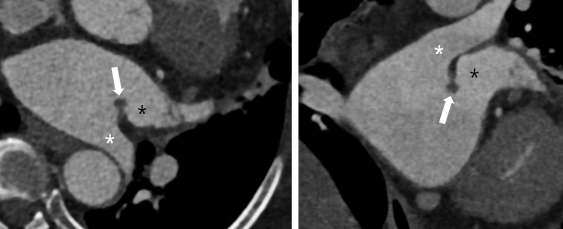

Coumadin Ridge

- Bande résiduelle dans l’oreillette gauche

- Sépare l’oreillette des ostiums des veines pulmonaires